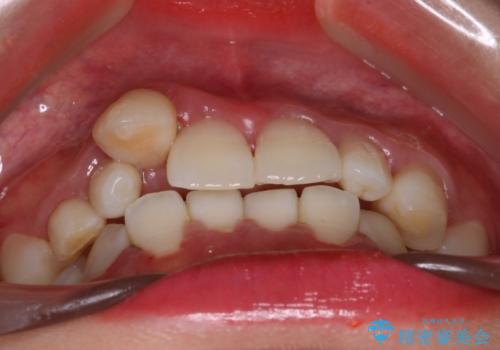

【インビザライン】八重歯が気になる

- 乳歯を抜歯してスペースを確保し八重歯の改善を行いました。

インビザラインをしっかり使用していただいたので、きれいな歯並びになりました。